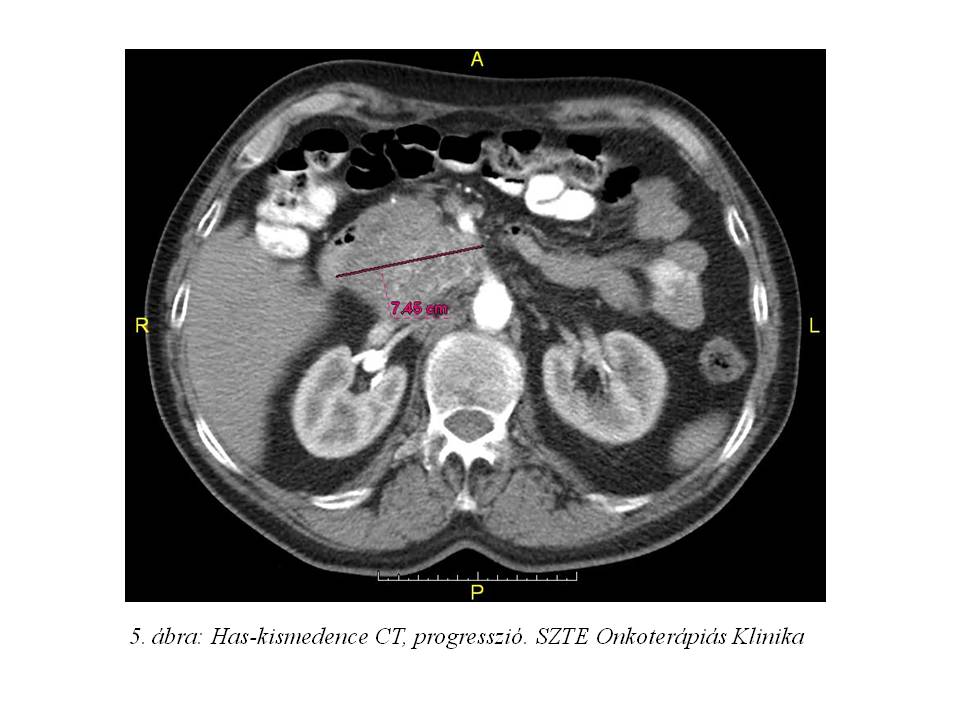

2014.07.23-án elvégzett has-kismedence CT vizsgálat (5. ábra) progressziót igazolt, ezért 2014.08.04-től kezelését a továbbiakban magas dózisú lanreotid kezelésre váltottuk.